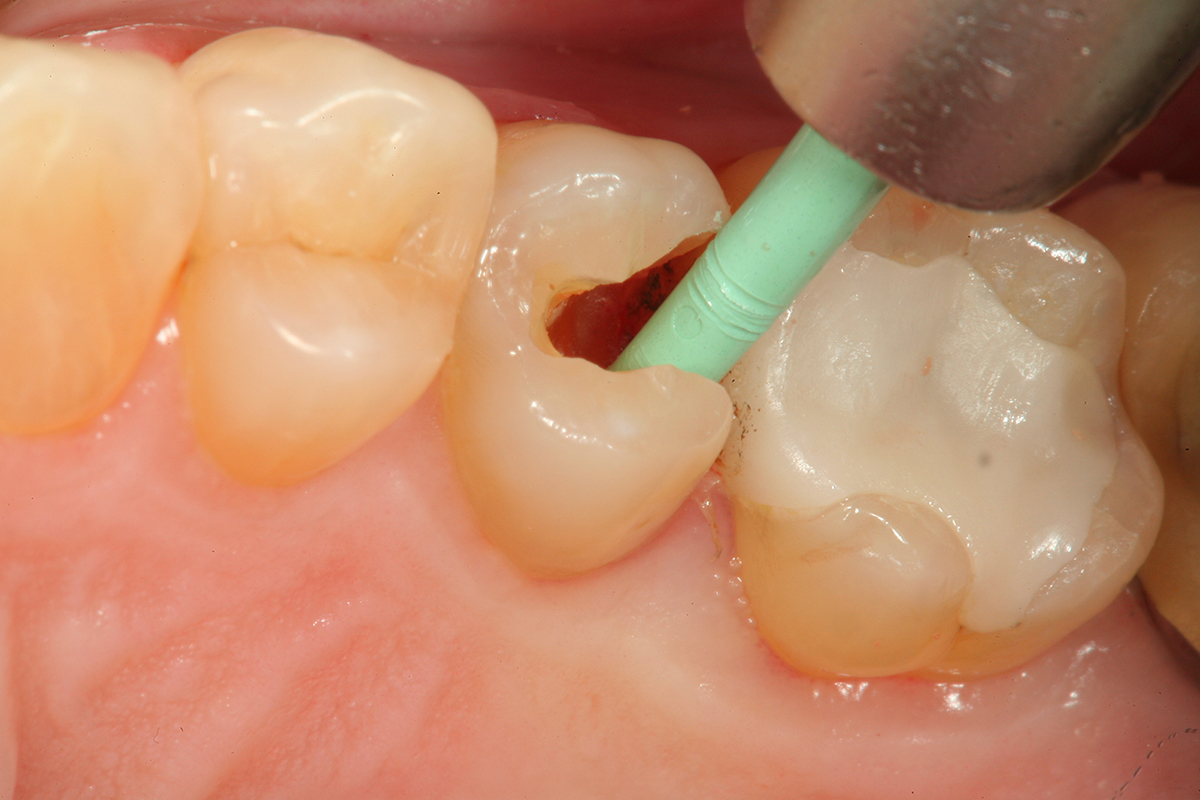

Fig 3. The lesion is excavated with a Smart BurII® (SS White) to remove infected dentin only.

Figure 3